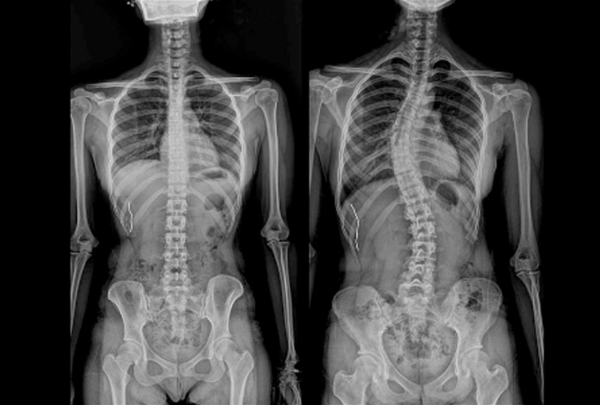

척추측만증은 척추의 비정상적인 측면 만곡을 특징으로 하는 근골격계 질환입니다. 척추가 등을 따라 곧게 뻗어 있는 대신 왼쪽이나 오른쪽으로 휘어져 문자 "S" 또는 "C"의 모양과 비슷할 수 있습니다. 만곡의 정도는 다양할 수 있으며, 어떤 경우는 경미한 반면 어떤 경우는 더 뚜렷하여 개인의 삶의 질에 잠재적으로 영향을 미칠 수 있습니다.

척추측만증 진단

척추측만증 진단에는 일반적으로 신체 검사가 포함되며, 만곡 정도를 평가하기 위해 엑스레이 또는 기타 영상 검사가 포함될 수 있습니다. 조기에 발견하면 적시에 개입하여 더 나은 결과를 얻을 수 있으므로 조기 발견이 중요합니다.